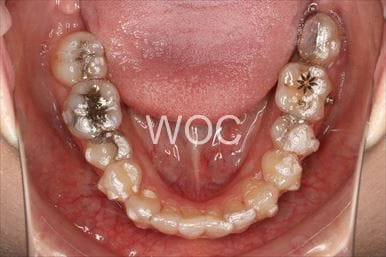

八重歯・叢生舌側矯正

上下舌側矯正を希望。奥歯を後方へ移動し、非抜歯で治療を終わることができました。

- 年齢:17歳女性

- 主訴:前歯が斜めになっている

- 基本矯正料金:1,250,000円

- 治療期間:1年7ヶ月

- 非抜歯